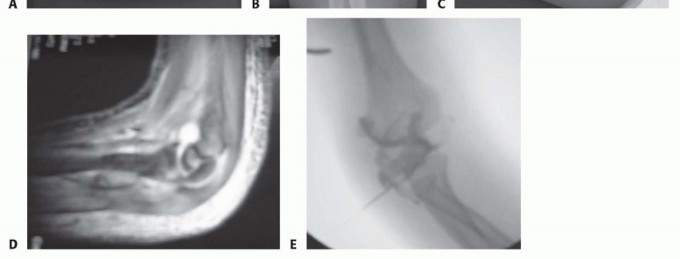

Standard radiographic evaluation requires high-quality, true anteroposterior (AP) and lateral views of the elbow. However, because the lateral condyle displaces posterolaterally due to the vector of the extensor mass, an internal oblique view is arguably the most sensitive radiograph for detecting maximum true displacement. The internal oblique view profiles the lateral condyle optimally and frequently reveals significant displacement that appears falsely minimal on standard AP and lateral projections.

In clinical scenarios where the displacement is borderline (exactly 2 mm) or the integrity of the articular hinge remains questionable, intraoperative arthrography is a powerful adjunct. Arthrography allows dynamic, real-time visualization of the cartilaginous surfaces. If radiopaque dye does not leak into the joint space across the fracture line, the cartilaginous hinge is intact, and closed reduction with percutaneous pinning (CRPP) may be safely attempted. Advanced imaging, such as MRI, is rarely indicated in the acute setting but can be utilized in delayed presentations to assess physeal anatomy and vascularity.

The reduction must be assessed visually at the articular surface. Anatomic restoration of the radiocapitellar and ulnohumeral joint line is the primary, non-negotiable goal. Once the articular surface is perfectly congruent, the metaphyseal fracture line should also interdigitate anatomically. Fluoroscopy is then used to confirm the reduction on both true AP and lateral views prior to final fixation.